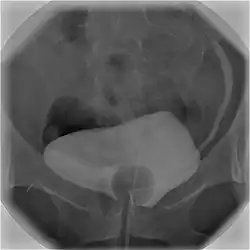

Zystographie

Als Zystographie bezeichnet man die Röntgendarstellung der Harnblase, wobei die im nativen Röntgenbild nicht erkennbare Blase mittels Kontrastmittelfüllung sichtbar gemacht wird. So können Lage, Form und Größe der Harnblase beurteilt werden, ebenso Wandveränderungen oder Fremdkörper.

Die Applikation des Kontrastmittels in die Harnblase erfolgt mit Hilfe eines Katheters. Dabei kommen in der Regel wasserlösliche, jodhaltige Kontrastmittel zum Einsatz, die verdünnt und in einem für eine pralle Füllung der Blase ausreichenden Volumen gegeben werden. Oft werden dann Röntgenaufnahmen sowohl im Stehen als auch im Liegen durchgeführt. Im Anschluss kann bei entsprechender Fragestellung die Ausscheidung des Kontrastmittels auf natürlichem Weg mittels weiterer Aufnahmen dargestellt werden, dann spricht man von einer Miktionszystourethrographie.